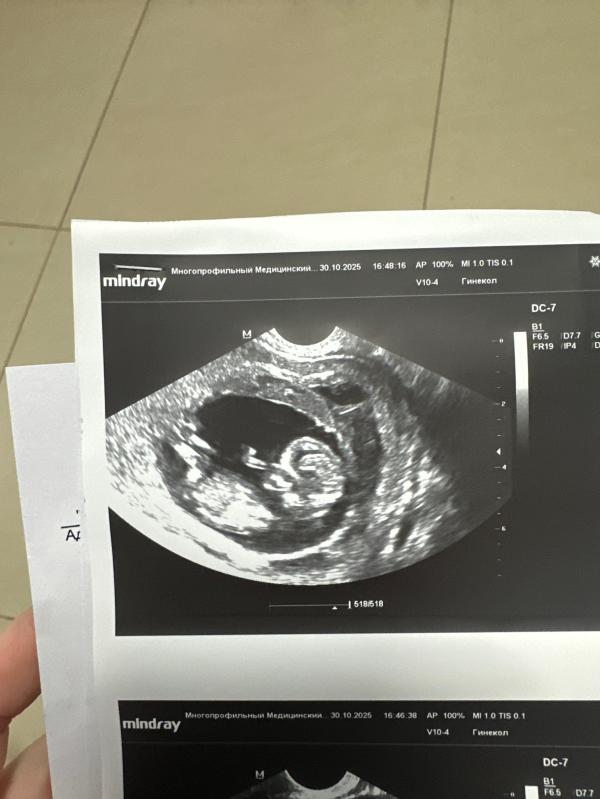

УЗИ показало уменьшение гематомы при беременности

Гематома меньше, лилипут кайфует